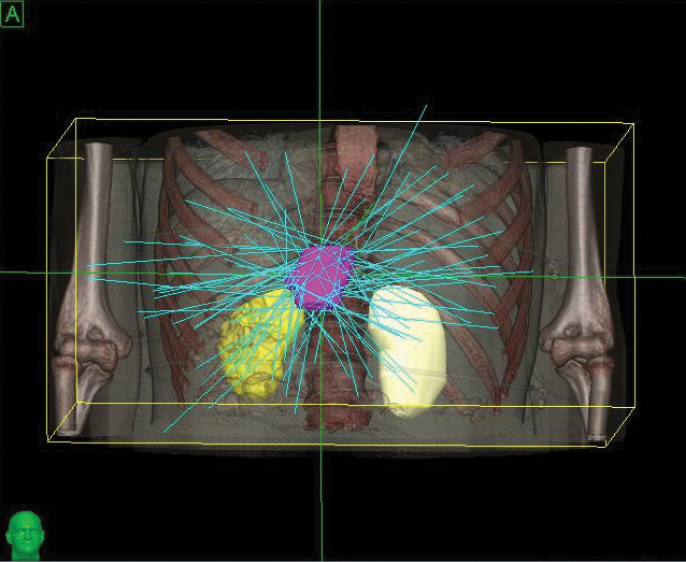

Phase 1 treatment covered the right lower lobe and hilar nodes, divided into two targets. The prescription was 48 Gy, delivered in four 12 Gy fractions for each of the two targets. Bilirubin fluctuations were noted during the course of therapy, but gradually returned to normal after treatment. One month after radiotherapy, a CT scan showed tumor shrinkage. The left lobe had sufficiently enlarged in compensation, so the second stage of treatment was initiated.

Phase 2 treatment covered the right upper lobe, divided into two targets: The prescription was 39 Gy, delivered in three 13 Gy fractions for each of the two targets.

“The CyberKnife System’s ability to track and adjust the beam with fiducials is key to giving high-dose SBRT to the liver.”

– Li Yu, M.D., Chairman, Radiation Oncology, 302 Hospital of PLA